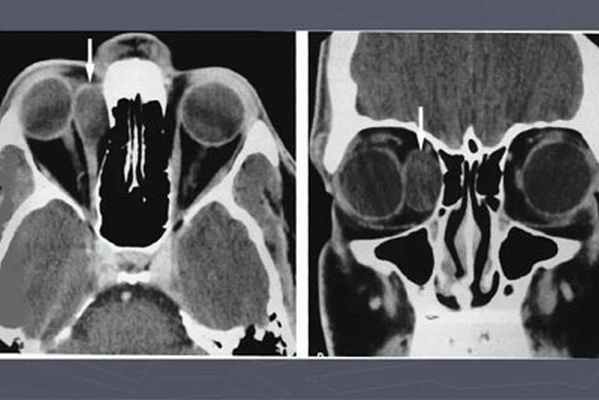

Диагностика

Поверхностные дермоидные кисты диагностируются при осмотре. Иногда, чтобы определить степень их инфильтрации, необходимо выполнить компьютерную томографию. В особенности это касается дермоидной кисты, располагающейся в области лица: такие опухоли обладают способностью прорастать в глубокие слои мягких тканей или носовые пазухи. В рамках подтверждения диагноза выполняют биопсию новообразования.